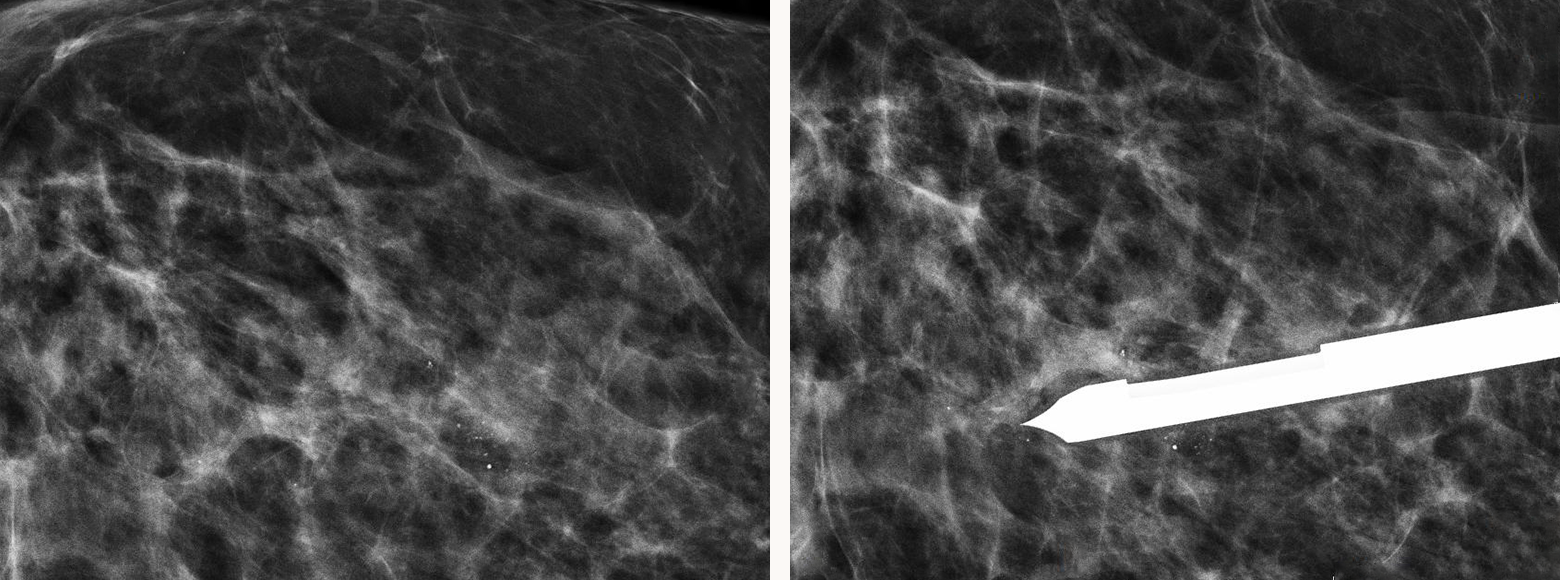

미세석회화 입체정위술이

가능합니다.

이제는 애플유에서

미세석회화 조직검사를 위해 수술을 해야 하는

불편함과 번거로움을 줄여드립니다.

애플유의

미세석회화 입체정위술은

믿을 수 있습니다.

미세석회화 입체정위술은 고가의 장비만 있다고

다 시행할 수 있는 것이 아닙니다.

애플유에는 프리미엄 장비는 물론 고도의 기술력과

풍부한 임상 경험을 갖춘 믿을 수 있는 의료진이 있습니다.

미세석회화 입체정위술

미세석회화의 매우 세밀한 진단

- 미세석회화 입체정위술

- 0기 암을 진단하는 고도 정밀 조직검사